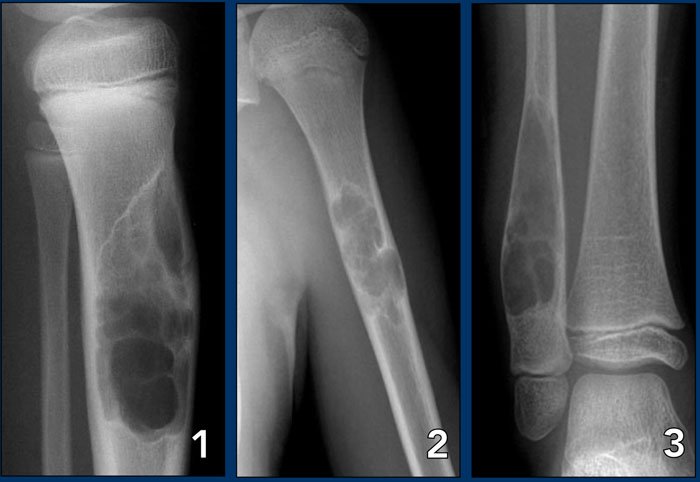

Bone tumors, whether benign or malignant, can be a cause of serious concern due to their potential to affect mobility, bone strength, and overall health. Early identification and the right treatment approach are crucial to prevent complications and ensure the best outcomes. At Summit Orthopaedic Hospital, we specialize in the diagnosis, evaluation, and management of bone tumors, using a multidisciplinary approach that combines clinical expertise, advanced imaging, biopsy techniques, and evidence-based treatment planning. We are equipped to handle the entire spectrum of bone tumor cases.